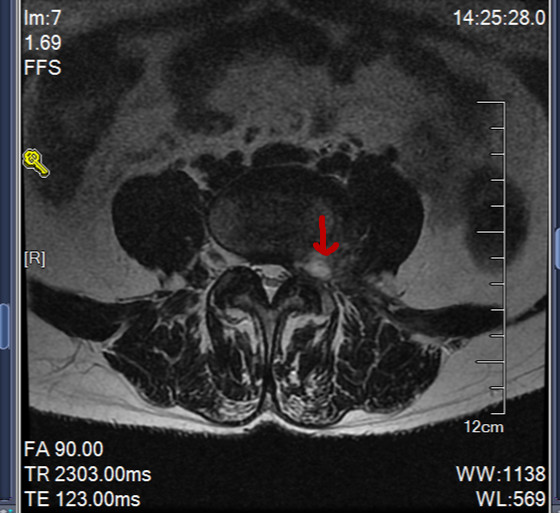

56岁的张阿姨(化名)腰腿疼病史好几年了,一直没查出来原因,先后去了大大小小的医院看过病,都告知腰肌劳损,回家养一养就好了,这一养就是好几年,症状没好转,反而最近1个月明显加重了,已经到了走路发瘸的地步,每天靠吃止疼药度日,后来在听病友说我们医院治疗腰腿疼效果好就来我们医院看病,经过查体,我们高度怀疑腰椎间盘突出,给患者做了个腰椎磁共振果然发现了元凶,就是这种极外侧的特殊类型腰脱

发现了元凶后我们给患者做了椎间孔镜手术,这种情况是椎间孔镜的绝对适应症,术后患者腿马上可以抬高80°以上(术前只能抬高30°),术后第二天下地行走正常(术前不敢下地,勉强下地也是走路发瘸)。

总结:对于极外侧的间盘突出,临床是很容易漏诊的,普通的骨科医生对这种情况也是认识不足,需要专业的脊柱外科医生才能确诊,椎间孔镜局麻即可解决,创伤小,术后恢复快。